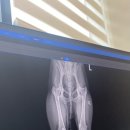

• 서현동물의료센터 | 청주 서현동물의료센터 강아지 건강검진 후기, 노견 단비의 꼼꼼한 체크업 리얼 리뷰!

하이루입니다!🤗 ​ 오늘은 우리 집 귀염둥이 단비가 청주 서현동물의료센터에서 건강검진을 받고 온 후기를 공유하려고 해요~ ​ 단비는 이제 열살을 훌쩍 넘긴 노령견이에요! 요즘은 작은 변화도 신경 써주려고 나름 노력하고 있어요💛 지난번에 유리를 밟아서 피가 났었던 발바닥 꿰맨 부분도 다 나았지만...! 최근엔 산책...

• 서현동물의료센터 | 청주 가경동 서현 동물의료센터에서 강아지 건강검진하고 왔어요🐶

마감 매주 목요일 정기휴무​ ✔️주차장⭕️ ​ ​ 안녕하세요~~~! 하리보입니다😊 오늘은 저희 밥풀이,밥톨이 건강검진 받으러 청주 가경동에 이번에 새로 개원한 서현 동물의료센터에 다녀왔어요‼️ 네이버로 여러 곳 검색해 보고 후기 보고 선택한 곳이에요 ‼️ 지금 건강검진 할인 이벤트도 진행하고 있어요. 다른 병원 기본 검진...

• 서현동물의료센터 | 청주 가경동 동물병원 추천-서현동물의료센터 정밀검진+상담 중심 후기

청주 가경동 서현동물의료센터 8살 시바견 땅콩이의 첫 정밀 건강검진 후기 ​ 땅콩이는 2018년에 데려온 파양견이에요. 철장에서만 지내던 아이였고, 기본적인 교육이나 산책 훈련조차 되어 있지 않은 상태였습니다. 처음 데려왔을 때 앞니가 다 갈려 있었고, 털 상태도 거칠고 푸석푸석했죠. ​ 제가 가장 먼저 한 일은...